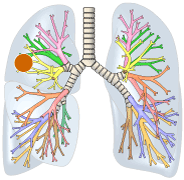

右図:肺門型肺がんは気管支の太い部分に発生した肺がんです。

肺門型肺がんは、気管支の太い部分に肺がんがあるので、痰の検査でがん細胞が見つかることがあります。気管支鏡の検査を行うと肺がんを直接観察できるので、がんの1部を採取して顕微鏡で検査することができます。